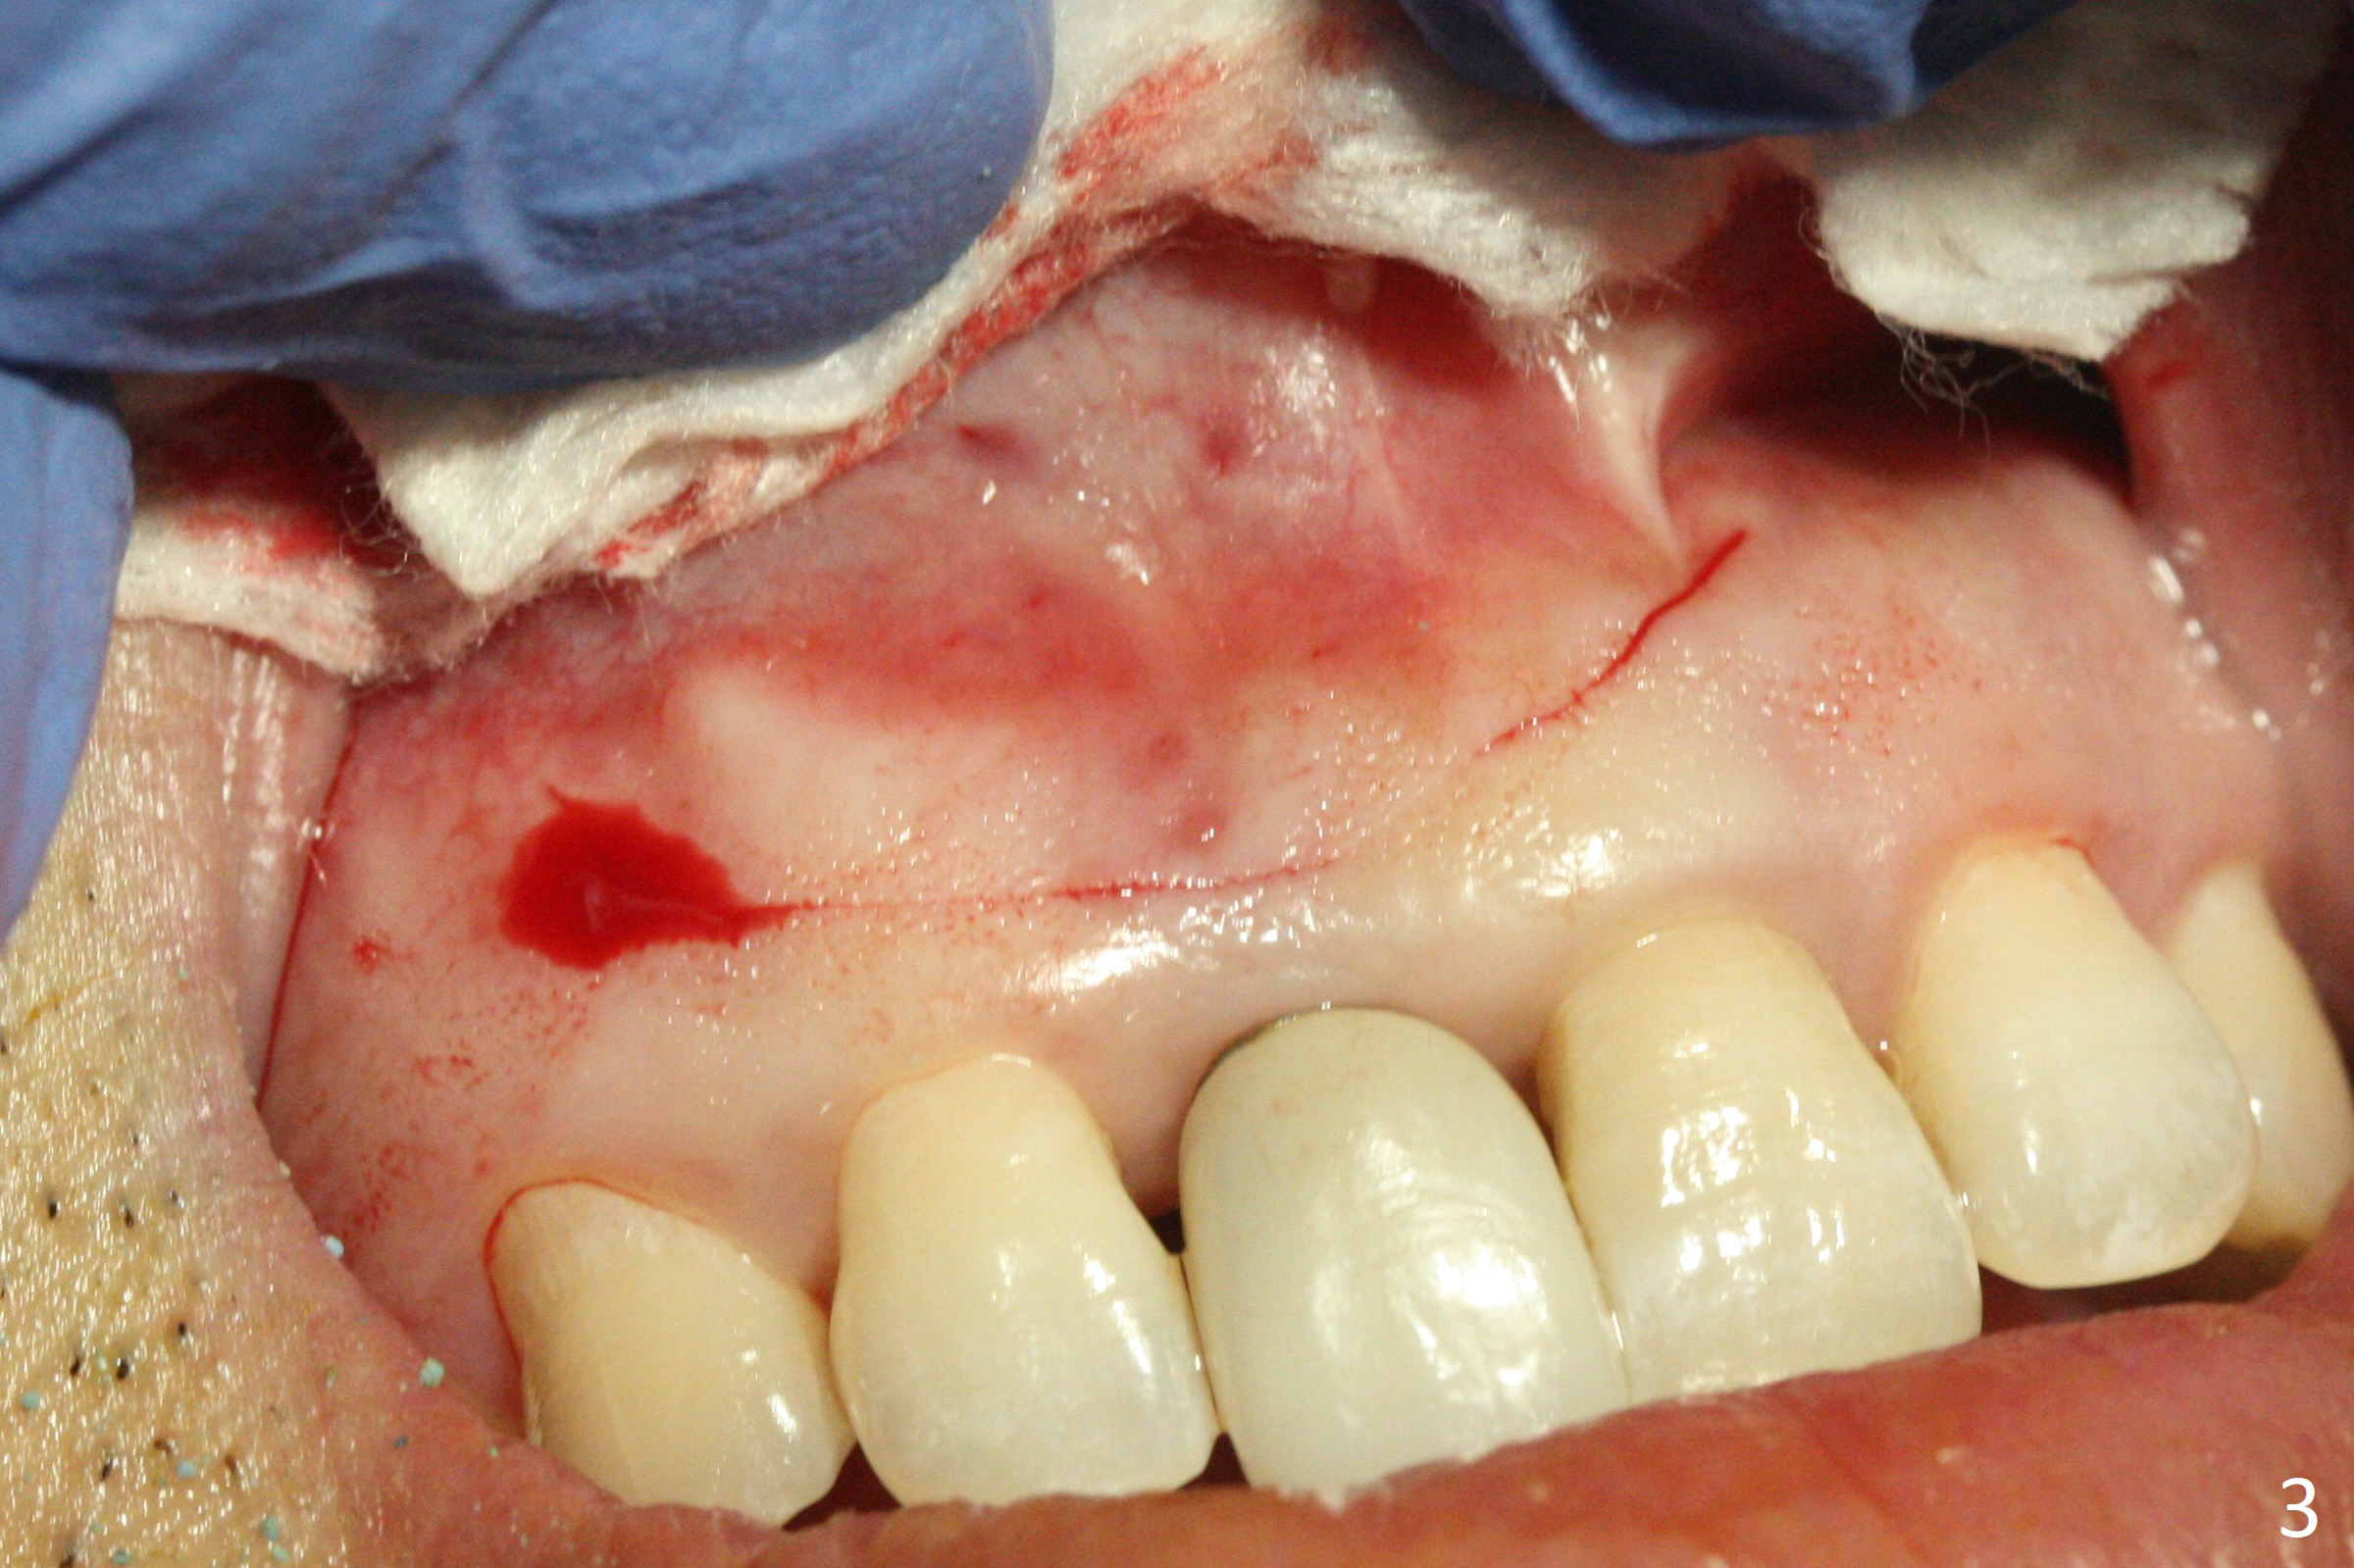

The patient returns because of purulent exudate from the buccal fistula (Fig.1 *) 1 year 9 months postop (1 year 3 months post cementation). Preop CT shows buccal thread exposure (Fig.2 arrowheads). To prevent postop gingival recession, a semilunar incision is made between the fistula and the gingival margin (Fig.3). After removal of granulation tissue (Fig.4), allograft in sticky bone form is packed (Fig.5). Following placement of PRF membrane and 6-month collagen membrane, the wound is closed (Fig.6). Since the implant (Fig.7 I) thread exposure is within bone (B) boundary (Fig.8 red dashed line), bone graft with PRF should be able to take care of periimplantitis (A: abutment). To prevent periimplantitis in similar situation, the immediate implant should be placed deep (not necessarily long, 18 mm) and narrower (3.5 mm instead of 3.8 mm). The defective buccal plate should be repaired with sticky bone and collagen membrane with incision if necessary. The wound does not dehisce 1 week postop (Fig.9) or 3 weeks postop (Fig.10, immediately post suture removal). Although bone graft seems to stay in place 6 months postop (Fig.11,12), the patient complains of bone graft expulsion sometimes. The buccal gingiva has deficiency (Fig.13). To fix it, make a remote incision (Fig.14 black line) and dissect before gingiva graft (Fig.15 dashed line). After removal of crown/abutment, the sinus track and implant surface are treated with Waterlase. A shorter cuff abutment is placed (4.5x5(4 to 3) mm) with a new provisional. The patient feels better with reduced sinus track 2 weeks postop (Fig.16).